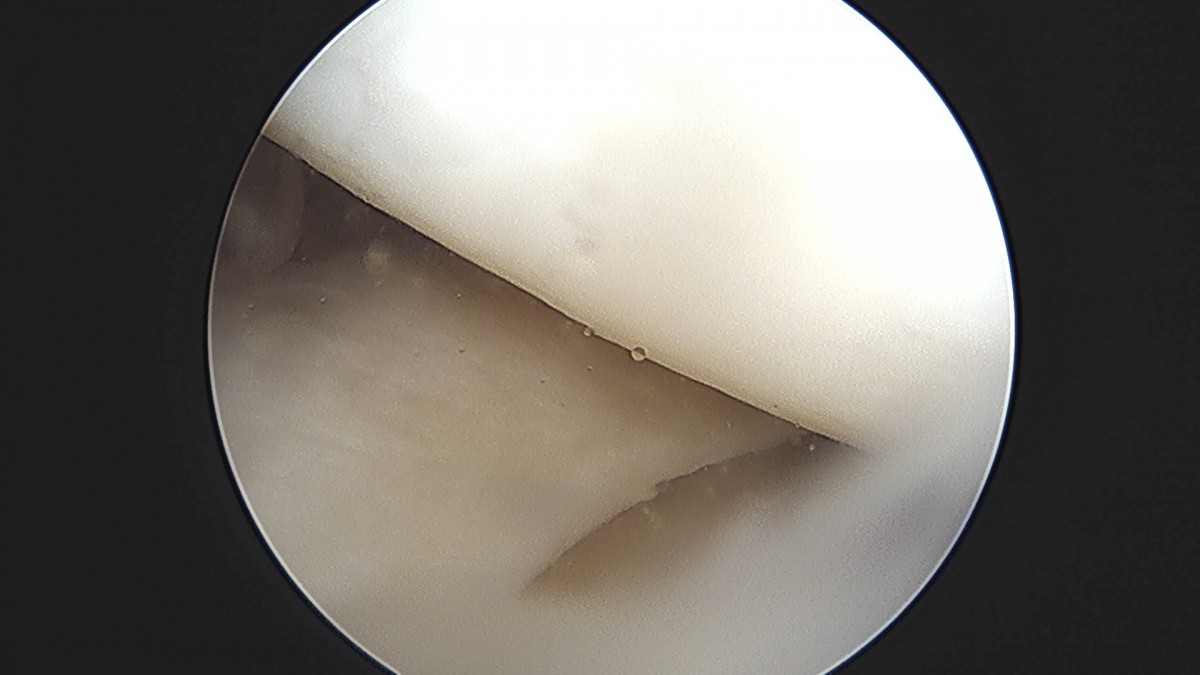

이재상원장님 무릎 낭종 제거술 김은O 환자

작성자 최고관리자 댓글 0건 조회 789회 작성일 25-09-16 15:20